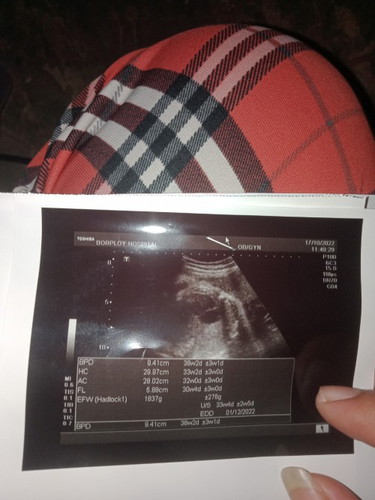

เเม่ๆช่วยดูใบซาวให้หน่อยค่ะะ เเบบนี้รู้เพศรึยังคะ #ท้องแรกคะ #ขอบคุณล่วงหน้านะคะ 35w3d💖💐

ในใบซาวไม่เห็นเพศค่ะ แต่น้องน้ำหนักน้อยไปหน่อย น้ำหนักตามเกณฑ์ของ 35 W คือ 2,383g